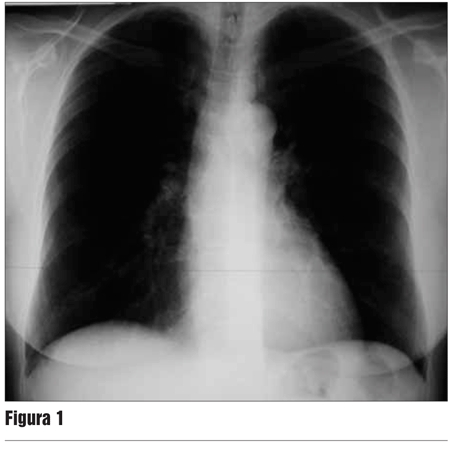

Se realizó screening para TB latente previo al inicio del tratamiento que incluyó: historia clínico-epidemiológica negativa, intradermorreacción con derivado proteico purificado (PPD) 00 mm y radiografía de tórax sin elementos sugestivos de TB activa ni secuelar (figura 1). Se interpreta como negativo para TB latente y no se realiza quimioprofilaxis.